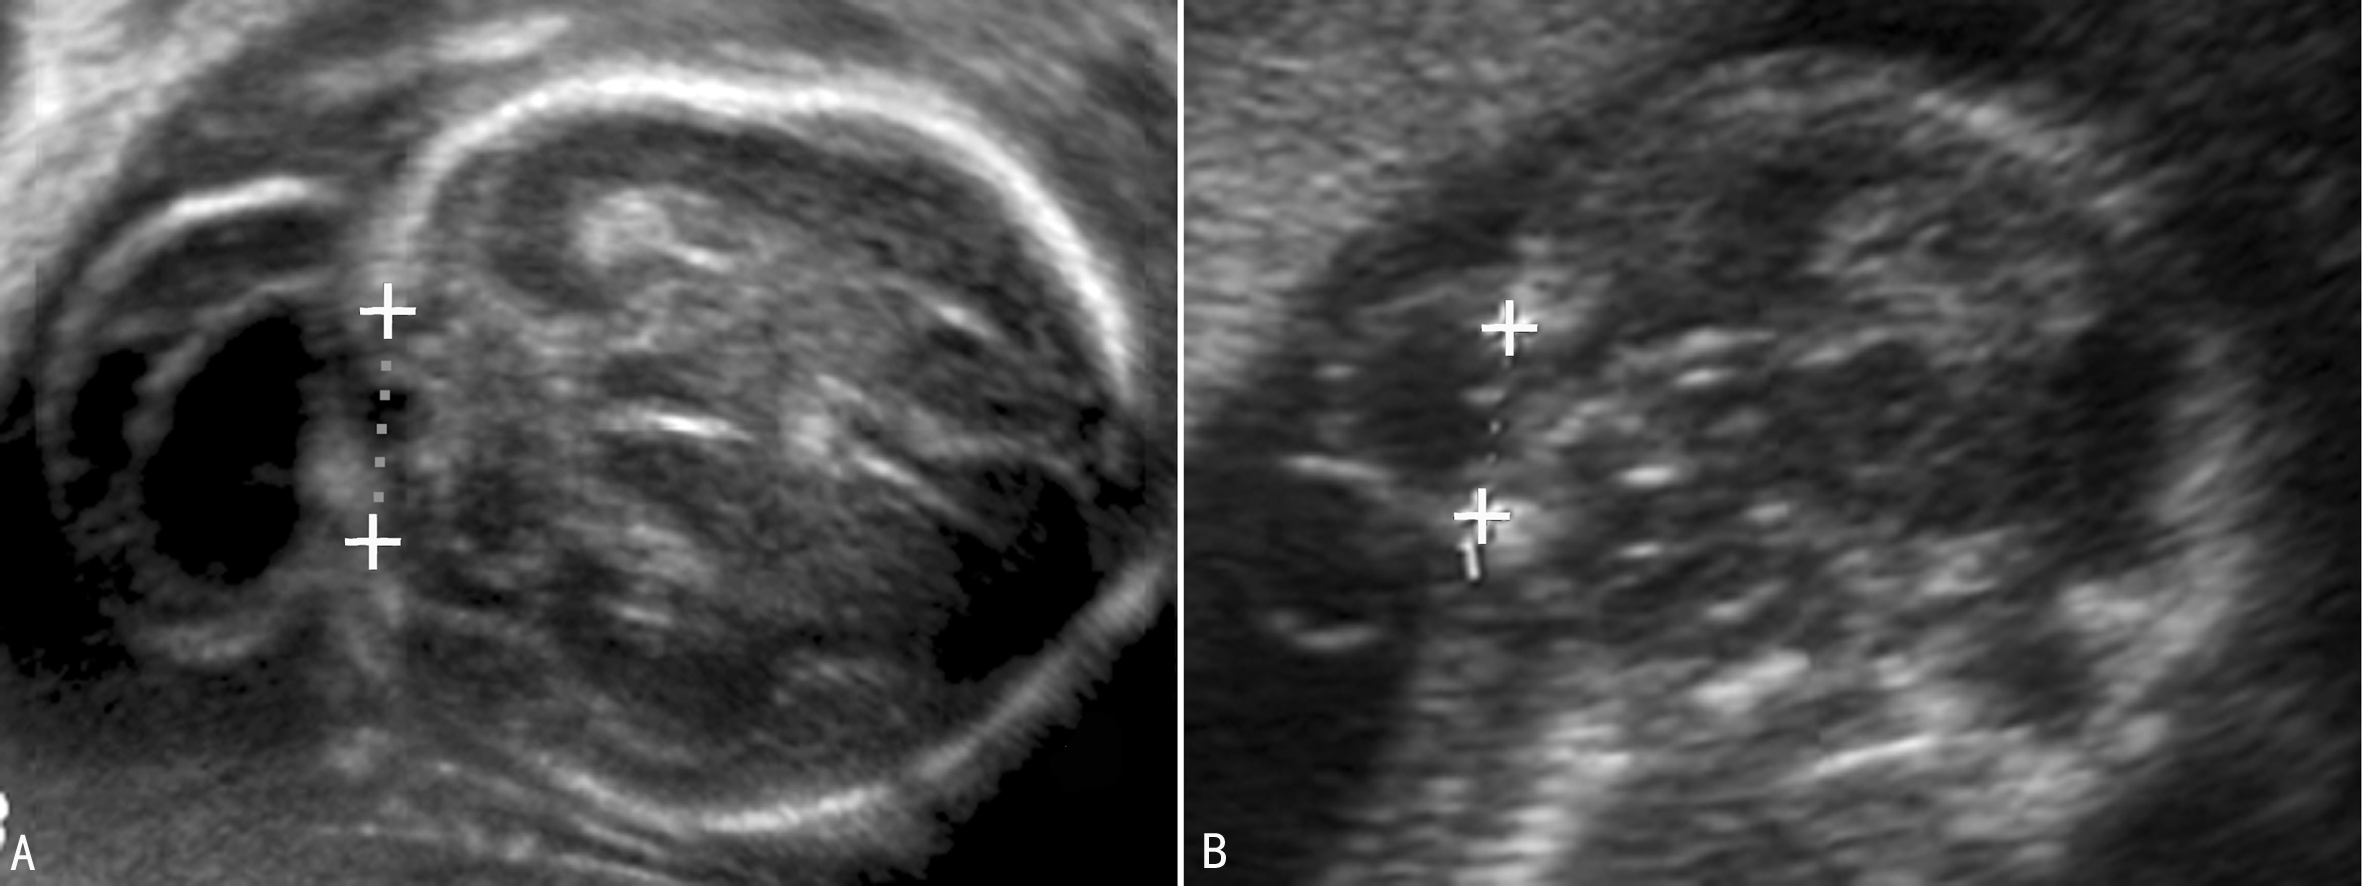

早孕期头颅小或者颅骨形态不规则,在头部轮廓外可显示包块样回声;随着胎儿的生长图像显示的愈加典型。经阴道超声可以看到早孕晚期的颅骨缺损处。胎儿颅骨显示后可以在颅骨外显示包块回声,局部颅骨显示缺损(图1),通过相互垂直的两个断面测量颅骨缺损的大小可以评估缺损的面积及突出物的大小(图2,图3)。有些小的缺损不能显示,仅能看到颅骨旁突出去的小囊样结构。突出的回声内部由于疝出的组织不同而有不同的表现,呈囊性或者囊实性混合回声(图1),“囊套囊”或者“靶环征”提示第四脑室脱垂,突出至颅底及眼部的脑膜膨出常难以于产前做出诊断。70%~80%伴有脑室扩张(图1A),25%伴小头畸形。除脑部异常回声外,其他部位检查可以发现伴发的畸形。

图2枕部缺损大小的测量(A:左右径 B:上下径)